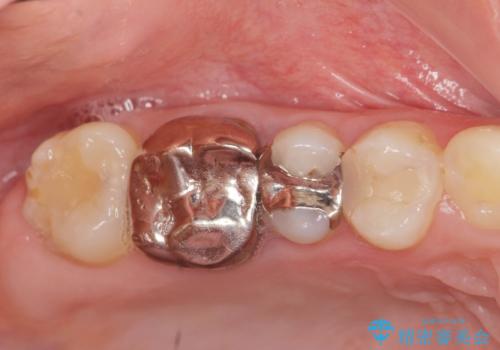

歯周外科を行い歯ぐきの整備を行うセラミック治療

銀歯周囲の虫歯再発や、歯ぐきよりも深い虫歯、根尖性歯周炎と言った複合的な問題を、

歯周外科、精密根管治療、セラミック治療を行い、妥協のないセラミック治療を計画します。

- 63.8万円(ジルコニアクラウン×4・仮歯×4・歯周外科)費用は治療当時の料金となります

虫歯の再発可能性を限りなく低く抑えるためには、虫歯の徹底的な除去を行ったのちの精度の高いセラミック治療が必須です。

今回の治療では歯ぐきの問題を解決するため、歯周外科を行いました。